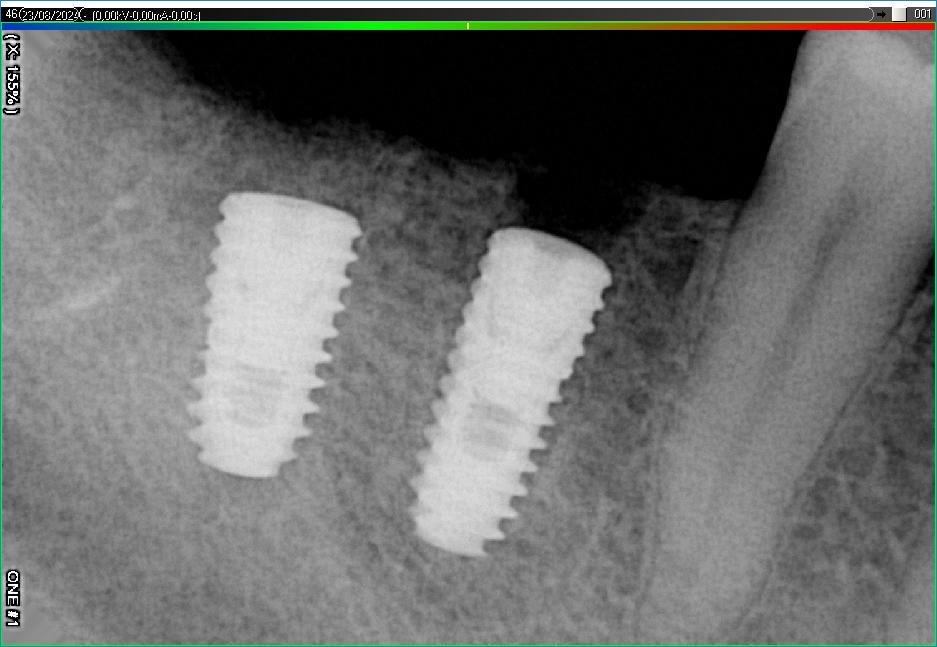

Імплантація